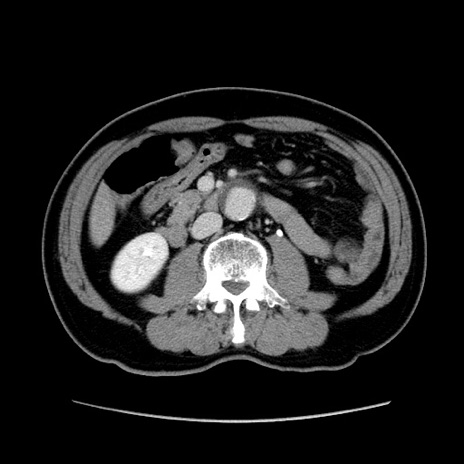

症例34(横断像)

【症例】60歳代 男性

【主訴】右鼠径部膨隆

【現病歴】1年程前より右鼠径部膨隆あり。自己にて還納可能だったため放置していた。3時間前より右鼠径部の脱出を認め、還納困難となり受診。

【既往歴】高血圧

【身体所見】右鼠径部に小児頭大の膨隆あり。弾性硬であり、用手還納は困難。左鼠径部にも膨隆を認める。脱出はなし。

【データ】WBC 15500、CRP 測定なし